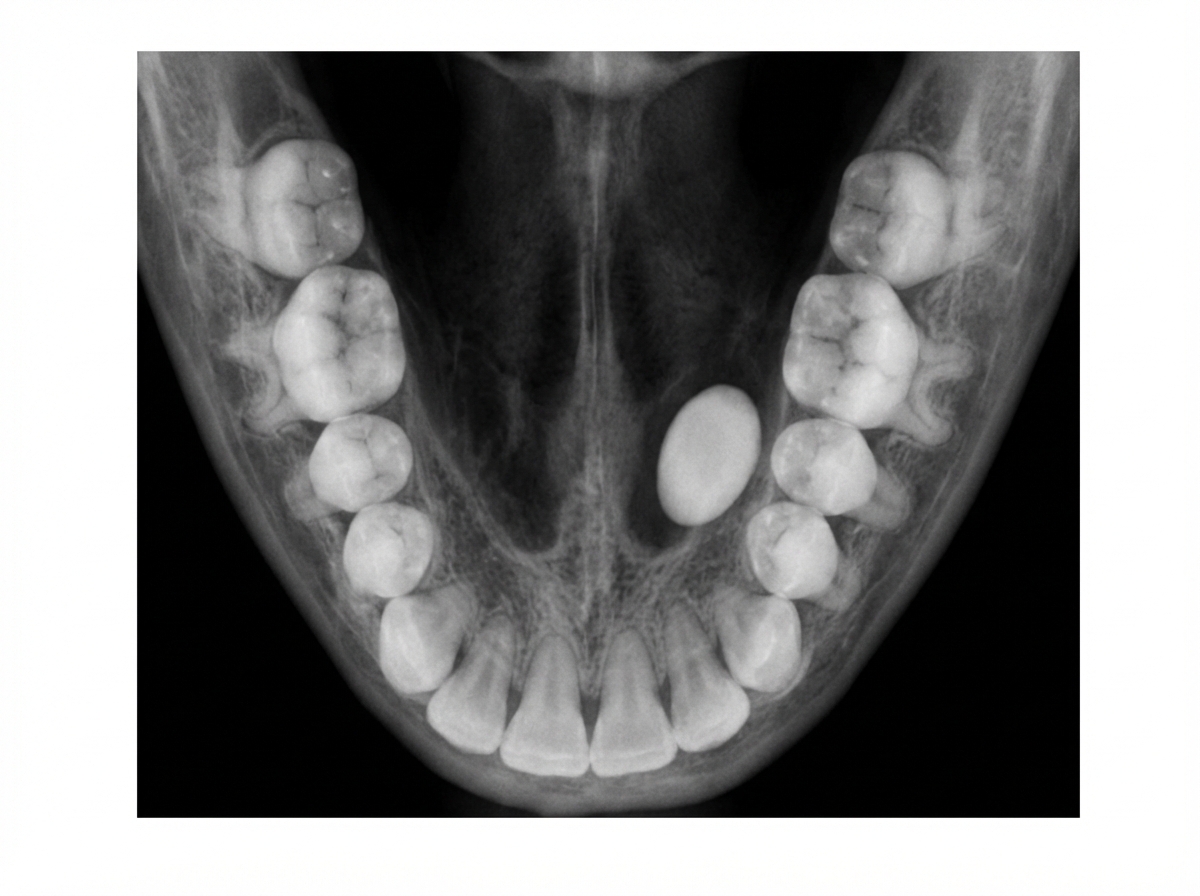

The following occlusal radiograph shows:

Explanation: ***Submandibular calculus*** - **Occlusal radiographs** are the gold standard for detecting **submandibular calculi** because they provide optimal visualization of **Wharton's duct** running along the floor of the mouth. - The **anatomical location** of the submandibular gland and its duct makes them clearly visible on occlusal projections, appearing as **radiopaque masses** in the expected pathway. *Parotid calculus* - **Parotid calculi** are located in **Stensen's duct**, which runs along the buccal surface and is **not optimally visualized** on occlusal radiographs. - **Lateral oblique** or **panoramic radiographs** are preferred for parotid gland pathology, not occlusal views. *Sublingual calculus* - **Sublingual calculi** are extremely rare compared to submandibular calculi and typically occur in **Bartholin's duct**. - The **sublingual glands** have **multiple small ducts** rather than one major duct, making calculus formation uncommon in this location. *None of the above* - The **occlusal radiograph** is specifically designed to show structures in the **floor of the mouth**, making submandibular calculi the most likely finding. - Given the clinical context and radiographic technique, **submandibular calculus** is the most appropriate diagnosis for this imaging modality.